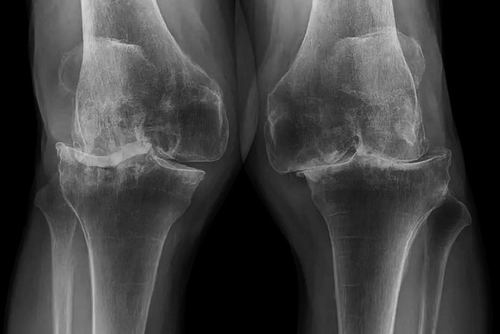

圖片來(lái)源:SCIENCE PHOTO LIBRARY

隨著年齡的增長(zhǎng),骨關(guān)節(jié)炎是膝關(guān)節(jié)疼痛的常見(jiàn)原因,它包括軟骨的磨損和撕裂。軟骨是覆蓋在骨頭末端的一層類似橡膠的物質(zhì),能夠防止骨頭摩擦。